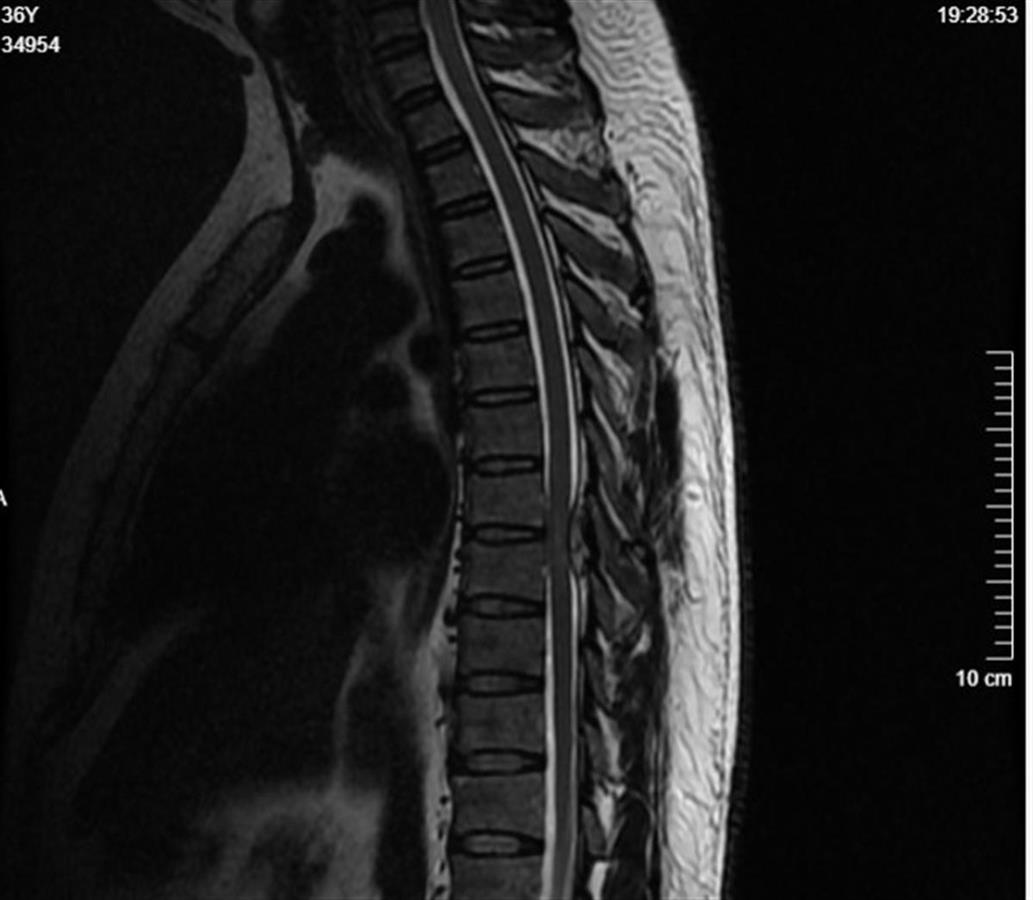

武汉市第四医院脊柱外科医生接诊后,对张先生进行了详细的检查,磁共振检查结果显示,张先生的脊柱胸椎段有异常影像改变,椎管狭窄导致脊髓神经受到压迫,已经出现了缺血变性;进一步检查发现张先生的尿酸值超标,结合脚踝胀痛等迹象,医生判断他腰部及下肢麻木是由痛风性炎症所致,即痛风石“长”在脊柱上了。

痛风石和炎性物质压迫和刺激脊髓神经,引发了下肢麻木乏力(通讯员供图)

据介绍,痛风石是痛风后局部形成的尿酸盐结晶,多数情况下痛风石会出现在脚趾、脚踝等部位,偶尔殃及脊柱。由于椎管内空间有限,痛风石和炎性物质压迫和刺激脊髓神经才引发了下肢麻木乏力,严重时甚至会导致截瘫。

在医生的建议下,张先生接受了胸椎管内病灶清除手术和椎管减压手术,术中医生发现痛风石如同石灰一样“糊”在他的椎管上,压迫了脊髓神经。清除痛风石、解除压迫后,张先生的症状有所缓解,随后将接受进一步的康复治疗和降尿酸治疗。